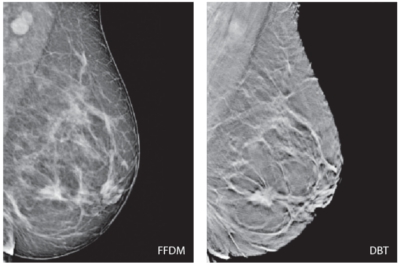

Tehnologia DBT oferă o calitate a imaginii superioară şi implicit informaţie clinică suplimentară prin comparaţie cu mamografia digitală (FFDM**), considerată deja clasică.

* DBT – Digital Breast Tomosynthesis

** FFDM – Full Field Digital Mamography